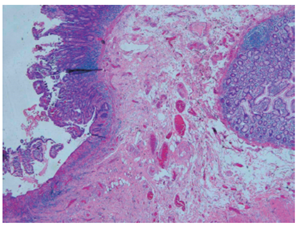

Se realizó una cirugía por vía laparoscópica evidenciándose macroscópicamente la presencia de estenosis de íleon de aproximadamente 1 cm con infiltración grasa sobre la serosa y el tatuaje adyacente. El reporte de patología del espécimen quirúrgico describió la presencia de alteración de la arquitectura de la pared de intestino delgado, con pérdida focal de las vellosidades con ulceración, acortamiento y ensanchamiento velloso; criptas ligeramente distorsionadas con disminución de las células caliciformes, fibrosis de la lámina propia con aumento del infiltrado linfoplasmocitario, además de metaplasia de glándulas submucosas e hipertrofia de fibras nerviosas. Estos hallazgos son compatibles con enfermedad inflamatoria intestinal crónica de tipo EC en fase activa (Figura 4).